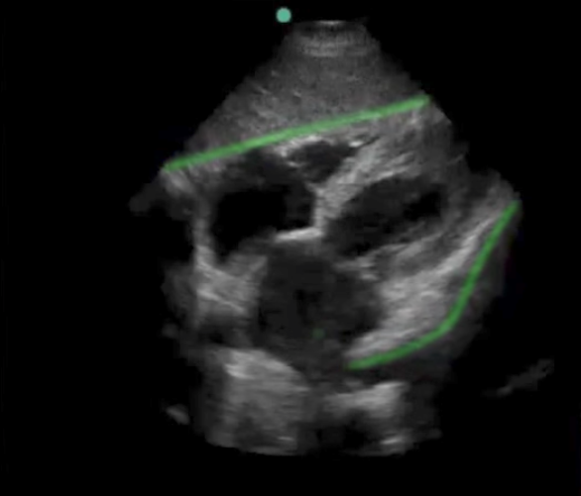

eFAST Subxiphoid Highlighted Pericardium Image

Highlighted Area: Pericardium